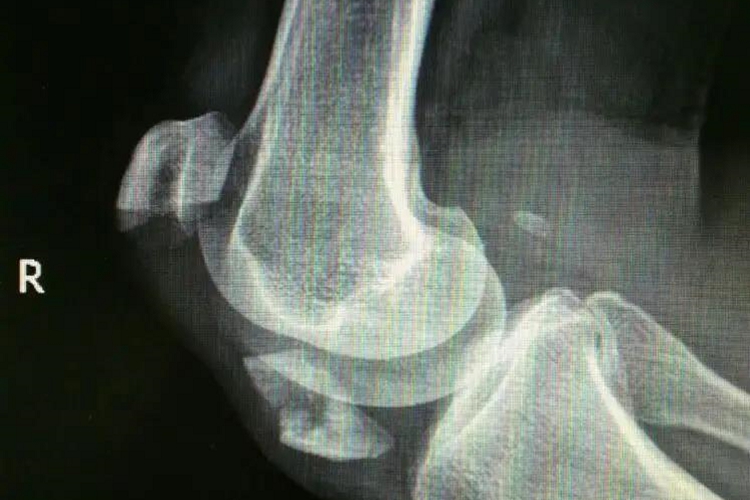

髌骨撕脱性骨折受伤后,膝前方肿胀明显,有瘀斑,膝关节不能活动。查体可见髌骨前方有压痛感,受伤早期可扪到骨折分离出现的凹陷,挤压髌骨使疼痛加重。由于骨折后关节内积血,可见浮髌试验阳性。通过X线检查可见髌骨的完整性被破坏,一部分髌骨完全断裂撕脱。